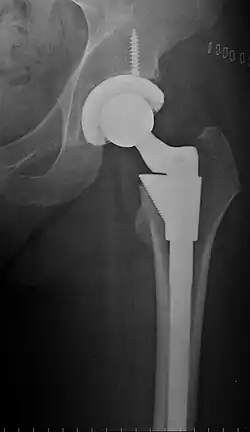

Post-operative projectional radiography is routinely performed to ensure proper configuration of hip prostheses.

The direction of the acetabular cup influences the range of motion of the leg, and also affects the risk of dislocation.[16] For this purpose, the acetabular inclination and the acetabular anteversion are measurements of cup angulation in the coronal plane and the sagittal plane, respectively.

![Acetabular inclination.[95] This parameter is calculated on an anteroposterior radiograph as the angle between a line through the lateral and medial margins of the acetabular cup and the transischial line which is tangential to the inferior margins of the ischium bones.[95]](./_assets_/Acetabular_inclination_of_hip_prosthesis.jpg)

![Acetabular inclination is normally between 30 and 50°.[95] A larger angle increases the risk of dislocation.[16]](./_assets_/Range_of_acetabular_inclination.png)